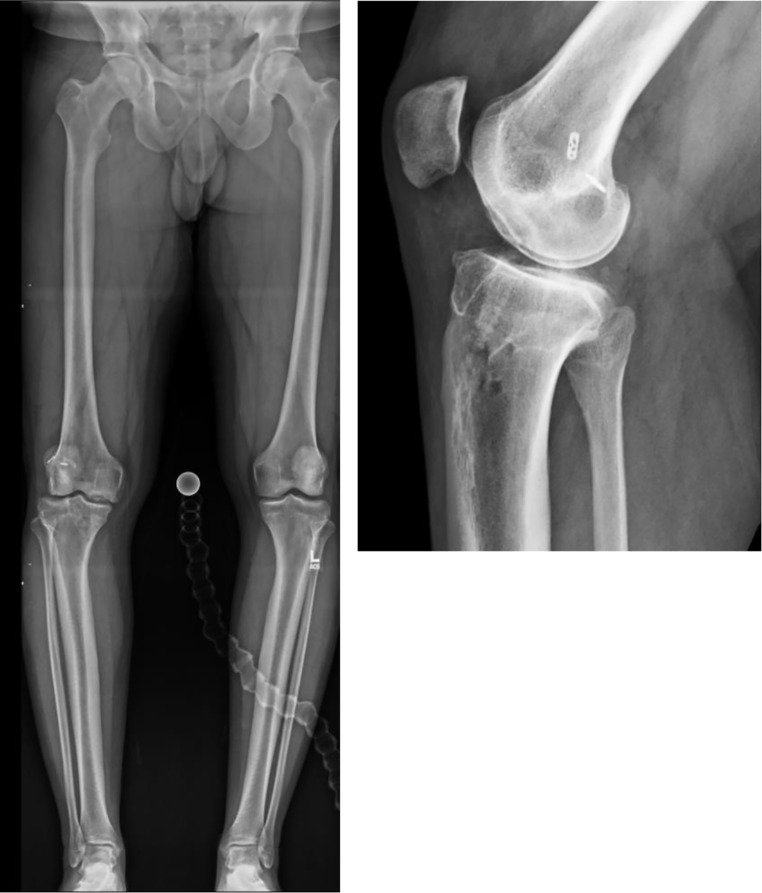

Purpose of review: Osteotomies around the knee are well-established techniques used to correct lower-extremity malalignment. While osteotomies of the proximal tibia and distal femur have traditionally been performed free-hand, the advent of Patient-Specific Instrumentation (PSI) in the form of custom 3D printed cutting guides and implants offers surgeons a greater ability to individualize surgical corrections to a patient's unique bony anatomy. This review aims to investigate the current state of the literature surrounding the use and outcomes of PSI for knee osteotomies and the benefits and drawbacks of PSI compared to traditional techniques.

Recent findings: Recent studies have demonstrated the potential benefits of PSI in knee osteotomy, including improvements in the accuracy of planned corrections, reductions in operative time and fluoroscopy exposure, and similar patient-reported outcomes. While increased costs and lead time represent drawbacks to the use of PSI, the technology continues to evolve such that these areas may improve over time. For osteotomy of the distal femur and proximal tibia, PSI offers surgeons an opportunity to improve surgical precision intra-operatively, with similar outcomes and complication rates as compared to traditional osteotomy techniques.